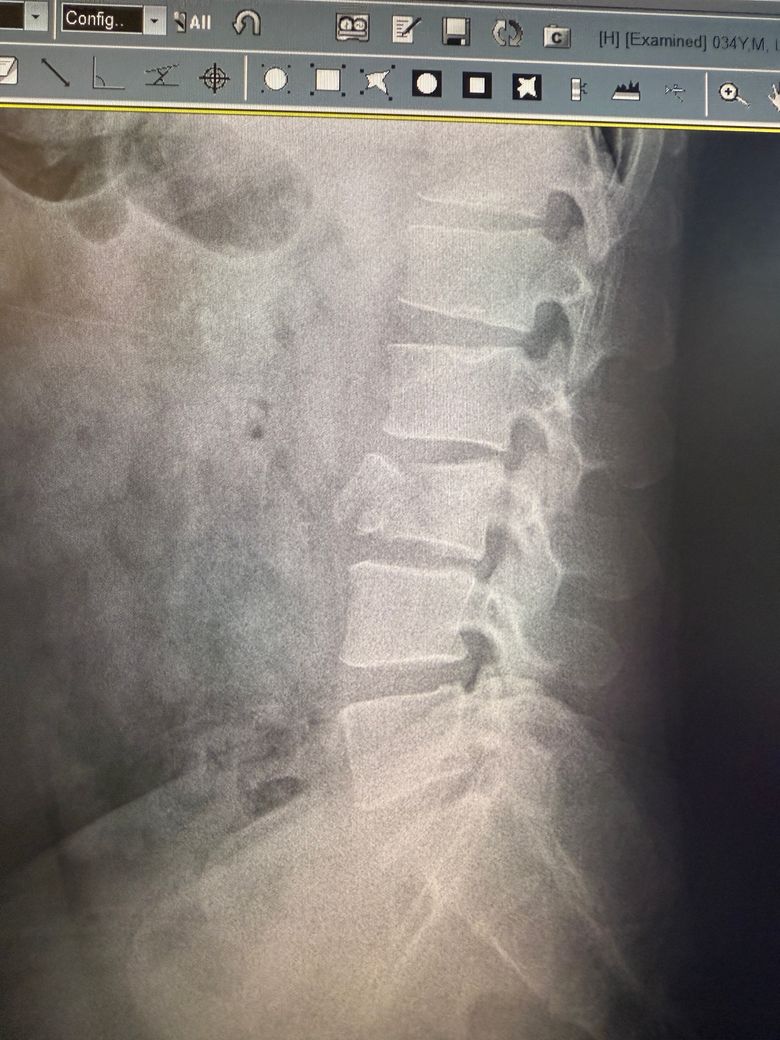

이정도면 수술해야되는거아닌가요?

척추가 저렇게 들렷는데 비수술로 그냥 굳힌다는데 추후네 디스크가 불안전하지않나요? 수술해야될거같은데..병원하나하나 믿기에 제가 부족한것같아 여기다가 한번물어봅니다 ㅠㅠ

척추가 들렸다는 것은 불안정성이나 전방 전위증 등이 의심될 수 있는데 신경 압박 증상이 없다면 보존 치료로도 충분히 관리될 수 있어요 단 통증이 지속되거나 악화된다면 수술 여부를 신중히 재검토해야 하니 척추 전문의 2차 소견도 추천드려요!

척추에 골절이 발생한 경우에는 안정을 취하며 골유합의 경과를 살펴보거나, 호전이 없는 경우에는 수술을 하는 경우가 있는데요, 병원에서 보존적인 치료를 유지한다는 소견을 들으신 경우라면 우선은 경과를 살펴보는 것이 좋습니다.

사진상 정확한 상태를 확인하기는 어려우나 척추뼈에 골절이 있는 상태로 보이며 일단 해당 병원에서 비수술적인 치료를 진행해보자고 하셨는데 불안한 상황이라면 다른 병원에 방문하시어 다른 전문의 선생님의 소견을 들어보시는 것도 좋을 것으로 생각됩니다.

병원에서 수술 없이 굳힌다고 했다는 것은 보존적 치료, 즉 물리치료나 운동요법, 혹은 코르셋 착용 등을 통한 안정화 치료를 의미할 수 있습니다. 이런 비수술적 치료는 증상이 심하지 않거나 신경 손상이 없는 경우에 우선적으로 시행되는 방법이에요

전위가 비교적 뚜렷하고, 증상이 계속되거나 악화되고 있다면 수술적 치료를 진지하게 고려해야 할 수 있습니다. 특히 다리 저림, 근력 저하, 감각 이상, 대소변 문제 같은 신경학적 증상이 있다면 수술이 필요할 가능성이 높죠

현재 치료 방식이 본인 상태에 맞는지에 대한 확신이 없다면, 척추 전문 병원에서 2차 진료를 받아보는 것이 안전하고 현명한 선택입니다. 정확한 진단과 함께 MRI 등 추가 검사로 신경 압박 정도를 확인하는 것이 치료 방향 결정에 큰 도움이 됩니다